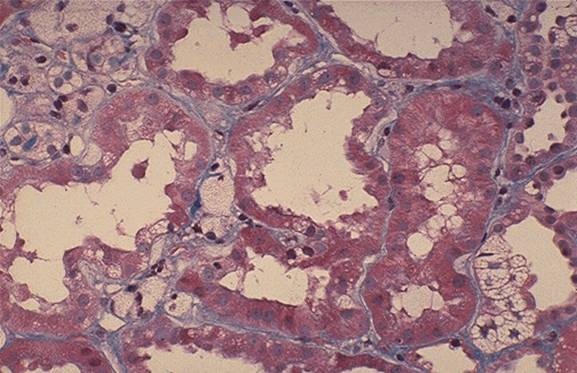

Aspect macroscopic si microscopic (Hematoxilina-eozina) in boala polichistica hepato-renala autozomal dominanta

n      M.O. evidentiaza chisturile ca diverticuli in capsula Bowman, tubul proximal, ansa Henle si tubul distal.

n      M.E. a demonstrat ca, pe masura ce cresc, chisturile nu comunica cu tubii de origine.